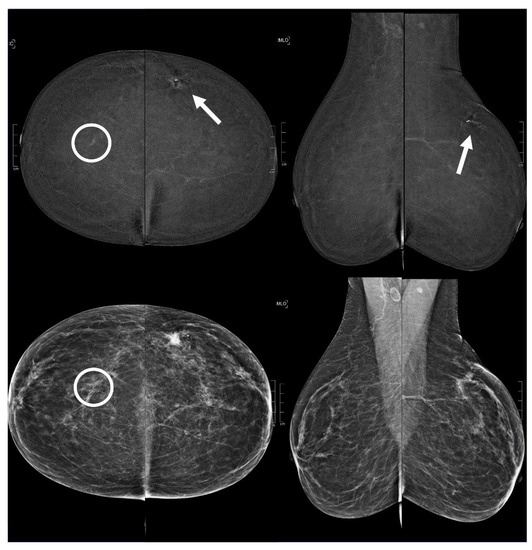

Figure 6.

A 60 year old patient. Contrast-enhanced digital mammography performed as preoperative staging for a B5 lesion in the left breast (arrows). In the early RC in the right breast, there was an enhancing asymmetry in the central quadrants with high conspicuity only visible in CC (circle), corresponding to an architectural distortion in low-energy images. This architectural distortion subsequently underwent VABB (tomosynthesis-guided vacuum assisted breast biopsy), which confirmed a ductal in situ carcinoma.